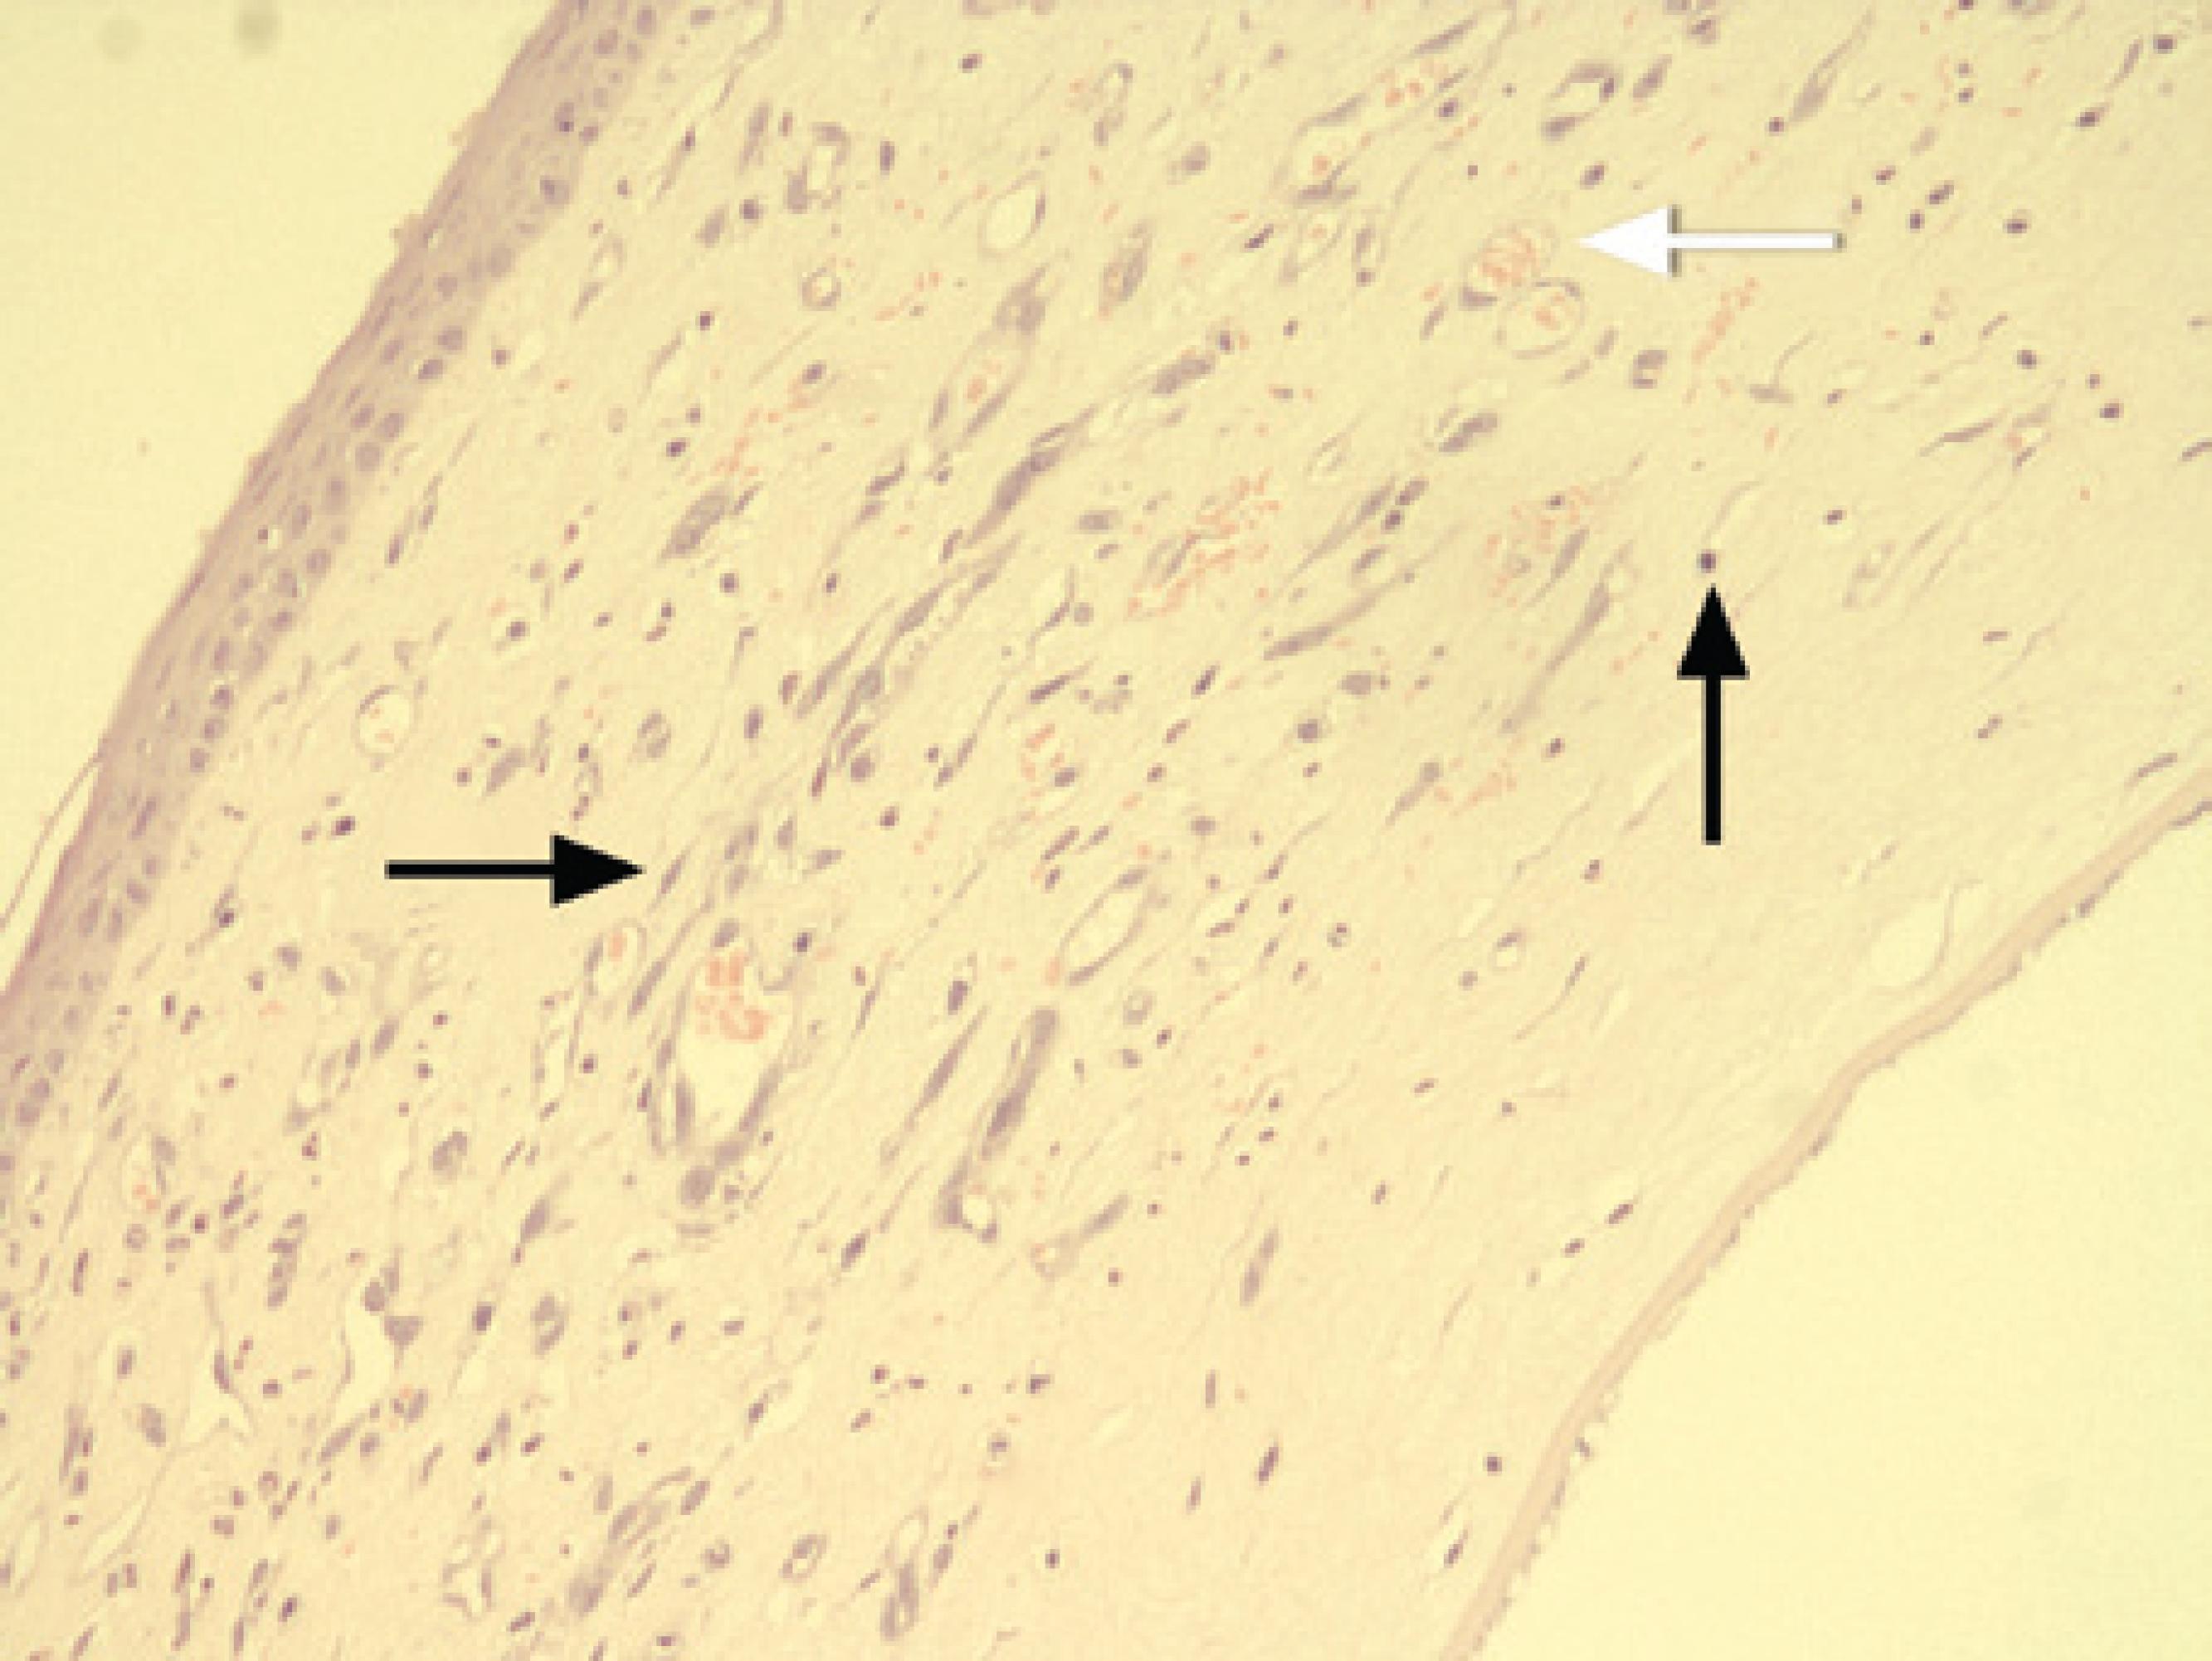

The rats were sacrificed on the eighth day using a high dose of pentothal sodium (Pentothal®, Abbott, Italy). The globes were then enucleated and fixed in 10% buffered formalin for 24 h. Corneas were then excised from the limbus and 5 µm thick sections were prepared. Sections were sliced from both the central region of the burn area and the intensive neovascularization area. They were then stained with haematoxylin-eosin and were analyzed using light microscopy. Sections were evaluated according to the intensity of neovascularization, the intensity of inflammation, and the fibroblast activity. Light microscopic inspections were performed on sections by an examiner (D.K.Y.) who was blinded to the study groups. The following scaling system, previously described in a study on corneal neovascularization, was used (Figure 4)(15).

Figure 4 Histopathological preparation of a cornea. Inflammatory cells (thin arrow), fibroblasts (black thick arrow), blood vessels, and stained erythrocytes within the blood vessels (white thick arrow) can be seen. The corneal specimens were stained with hematoxylin-eosin and examined using light microscopy (magnification × 400).

Intensity of neovascularization: + 1: minimal or close to negative vascularization. + 2: limited or focal vascularization in the subepithelial and prestromal areas. + 3: cases intermediate to groups 2 and 4. + 4: diffuse and intense vascularization.

Intensity of inflammation: + 1: minimal or close to negative inflammation. + 2: focal, low count of mixed inflammatory cell types such as lymphocytes, neutrophil leukocytes, and eosinophil leukocytes). + 3: cases intermediate to groups 2 and 4. + 4: intense, diffuse, mixed inflammatory cell types.

Fibroblast activity: + 1: minimal or close to negative fibroblast activity. + 2: focal fibroblast activity. + 3: cases intermediate to groups 2 and 4. + 4: diffuse and intense fibroblast activity.